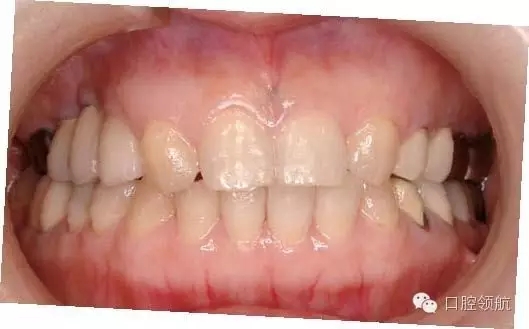

圖9 治療結(jié)束后7年6個(gè)月的口內(nèi)正面像